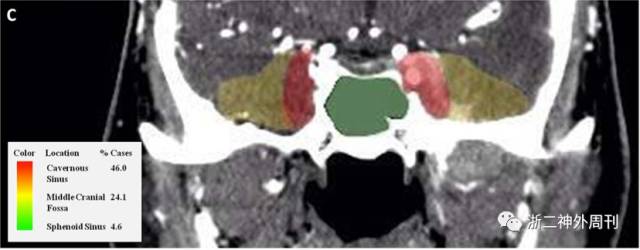

发生于颅内的IMT较为罕见,颅内IMT多见于眶内和颅底[1,2]。Desai SV等[3]总结了33篇文献共计87例发生于鼻窦和颅底腹侧面的IMT,得出IMT在颅底的分布热图(图4)。

图4. IMT侵犯颅底的分布热图

多数颅内IMT在CT上呈高密度病变,约有超过4/5伴有骨质破坏。MRI显示颅内IMT在T1像上呈等信号,T2像呈低信号,增强像上伴有强化,尤其当IMT位于海绵窦内时强化更为明显(图5)。

图5. 典型海绵窦IMT的影像学表现(箭头所指为IMT病变)